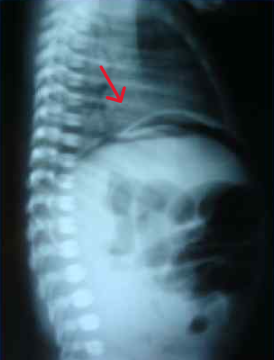

В возрасте 37 часов жизни с диагнозом кишечная непроходимость, перфорация полого органа для хирургической помощи перегоспитализирован в реанимационное отделение новорождённых ОДКБ в тяжёлом состоянии на ИВЛ. На рентгенограммах органов брюшной полости выявлен симптом «серпа», характерный для пневмоперитонеума (рис. 4).

|

Рис. 4. На рентгенограммах органов брюшной полости характерный признак пневмоперитонеума – симптом «серпа»